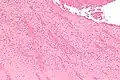

| A recent pulmonary thrombo-embolus with prominent lines of Zahn. The pale areas consist of fibrin and platelets. The red areas consist of erythrocytes. | |

Lines of Zahn are a characteristic of thrombi.[1] They have visible and microscopic alternating layers (laminations).[2][3] Platelets mixed with fibrin form lighter layers.[2] Red blood cells form darker layers.[2] Sometimes, the term "lines of Zahn" only refers to the lighter layers.[4]